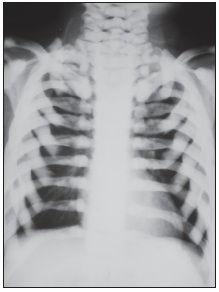

The child has osteopetrosis. The radiographs show diffuse osteosclerosis and dramatically increased bone density throughout the axial and appendicular skeleton. There is diffuse bone sclerosis in the hands with widening of the distal radial metaphyses (A, arrows) and a "bone-within-a-bone appearance"--typical of osteopetrosis--in virtually all the metacarpals and phalanges. Bone sclerosis is also apparent in the feet; the bone-within-a-bone appearance is most prominent in the metatarsals (B, arrows). A chest radiograph demonstrates diffuse bone sclerosis and numerous old fractures of the anterolateral ribs bilaterally (C, arrows).